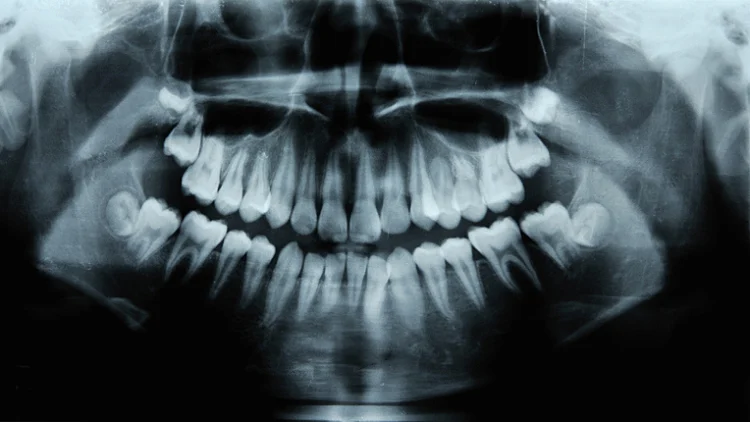

הודו: ילד בן שבע התלונן על כאבים בלסת, וכשהלך להיבדק הרופאים גילו בפיו לא פחות מ-526 שיניים. בן השבע אושפז בחודש שעבר בגלל נפיחות וכאבים בחלק הימני של הלסת התחתונה שלו. בצילום הרנטגן שערך לו הצוות הרפואי, הם מצאו מבנה דמוי כיס מוטמע בתוך הלסת התחתונה שלו, ובתוכו מאות שיניים לא תקינות.

אחרי גילוי הכיס, שני מנתחים הסירו אותו מפיו של הילד. לאחר מכן, הצוות הרפואי רוקן את השקיק ובחן את הממצאים במשך שעות ארוכות, על מנת לאשר את תכולתו. "היו סך הכל 526 שיניים בגדלים שונים, ממילימטר אחד עד 15 מ"מ. אפילו לחלקים הקטנים ביותר שנמצאו היו את כל המרכיבים שמאשרים שמדובר בשן", אמרה פראטיבה רמאני, ראש המחלקה האוראלית במכללה לרפואת שיניים בהודו. הניתוח אמנם התרחש בחודש שעבר, אך לרופאים לקח זמן לפענח את המקרה הנדיר.